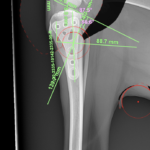

大型犬の前十字靭帯疾患(慢性経過)に対するCBLO #254 大型犬のCrCLDの患者さんに3.5 Rita Locking CBLOで対応しました。今後はリハビリテーションが非常に重要になります。生涯にわたって膝関節のケアを行なっていく必要があります。 症例カテゴリー 放射線治療整形外科軟部組織外科脳神経外科内科腫瘍外科救急・集中治療リハビリテーション科腫瘍内科内視鏡科脳神経科呼吸器外科中医・漢方猫の腎移植循環器科